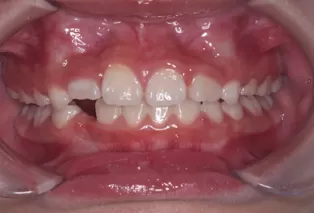

Intraoral photos